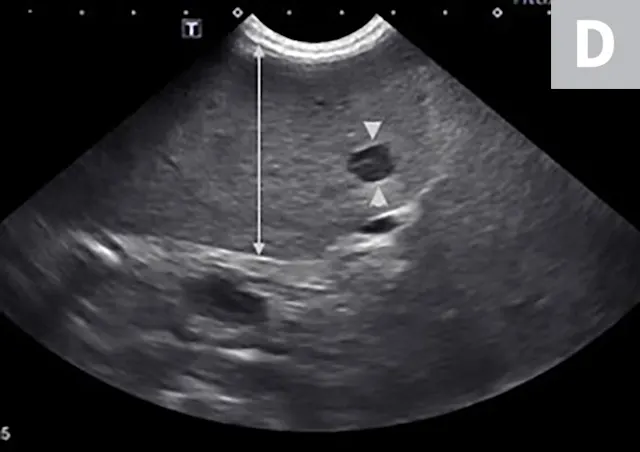

Imaging of a 1-year-old neutered male standard poodle presented with anorexia, lethargy, vomiting, hypoalbuminemia, hypoproteinemia, and cranial abdominal organomegaly. Transverse (A) and sagittal (B) ultrasound of the liver and gallbladder (GB). The liver is enlarged (with increased distance off the stomach from the diaphragm, rounded borders, and extension ventral to the stomach), diffusely hyperechoic, and homogenous. The gallbladder is moderately distended with a normal wall and content. Radiographs demonstrate hepatomegaly and splenomegaly (C). Abdominal ultrasound images revealed splenic enlargement with a mildly mottled architecture and a solitary hypoechoic nodule (D; arrowheads). The pancreas is enlarged and lobulated with multiple hypoechoic tracts and a peripheral capsule (E; between electronic cursors [X’s]). The jejunal lymph nodes are severely enlarged (F; between electronic cursors [X’s]), more than expected for a young dog. The combination of severe hepatosplenomegaly and lymphadenomegaly make systemic disease (eg, infectious, neoplastic) most likely. The appearance of the pancreas is due to pancreatic edema secondary to hypoproteinemia. Acute liver injury was diagnosed, and lymphoma was diagnosed based on hepatic and splenic cytology.